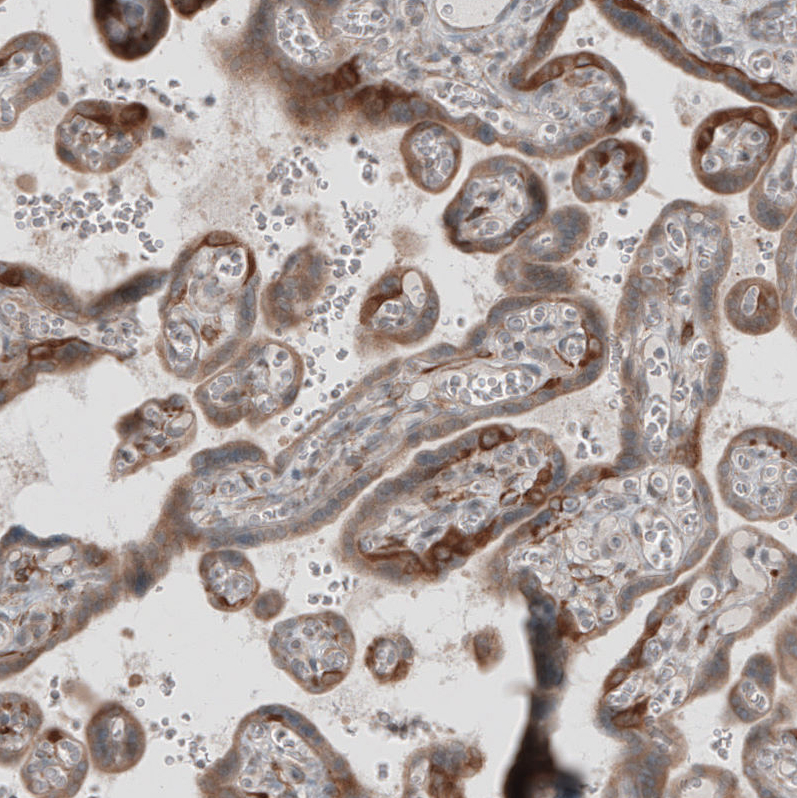

Immunohistochemical staining of human placenta shows moderate to strong cytoplasmic positivity in trophoblastic cells.